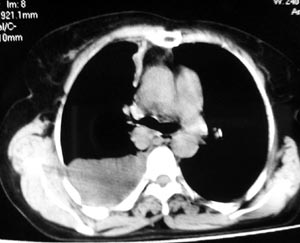

2 纵隔侧胸膜明显增厚

3 肋胸膜结节影

结合纵隔略宽、单侧胸水首先考虑肺癌。

同意9楼分析,肺癌,胸膜转移、胸水。

应该考虑一下胸膜间皮瘤,应该进行胸膜穿刺活检.

支持胸膜间皮瘤

右侧胸膜结节状增厚伴胸腔积液及纵隔、腋窝淋巴结肿大,考虑胸膜间皮瘤可能性大;建议胸膜活检。

右侧肺门淋巴结肿大,伴大量胸腔积液,同侧胸膜结节样增厚,有胸膜粘连,考虑肺癌.